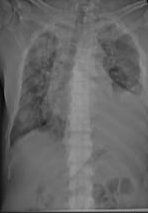

Repeat chest x-ray